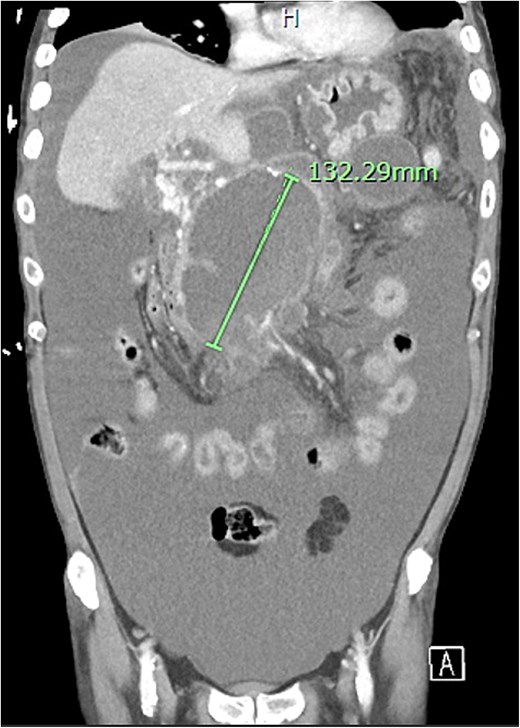

Further complications developed including non-cirrhotic portal hypertension, resultant ascites secondary to portal venous thrombus, and multiple peripancreatic collections (Fig. 10). The ascites and collections were managed by radiological drainage.

Extensive peripancreatic collections with large volume ascites.